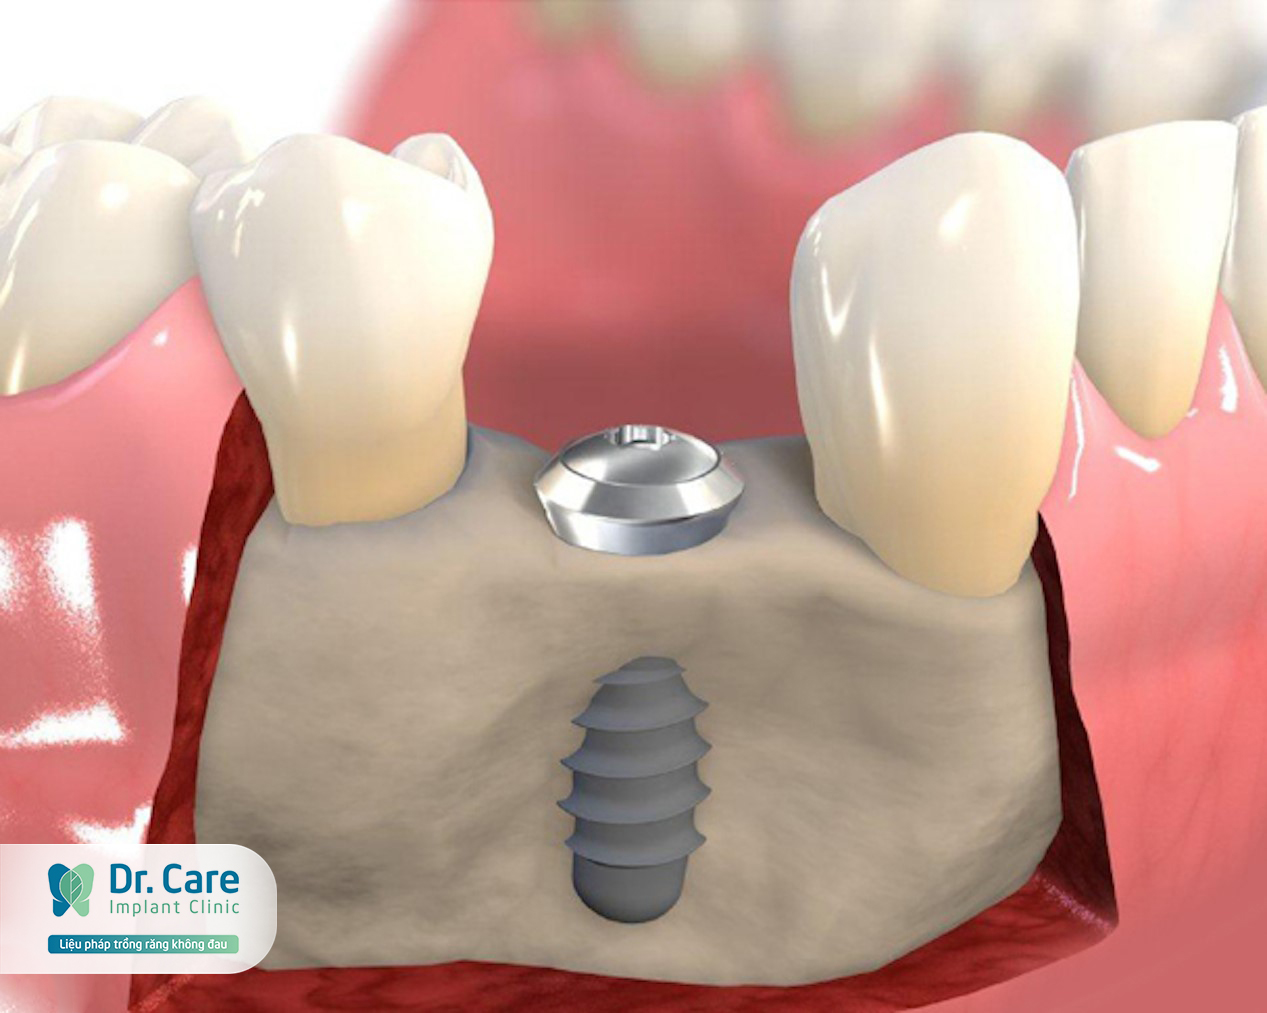

Фото и примеры имплантации зубов при пародонтите

Раздел: Необычные решения